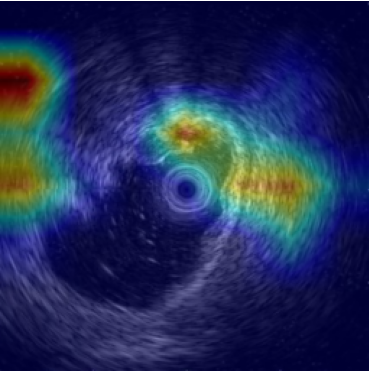

5.2 Visualization of attention weights

Fig. 5 presents a qualitative visualization of the learned word-to-region correspondences facilitated by our AGA framework. The top row shows the original medical images, including both chest X-rays (CXR) and endoscopic ultrasound (EUS) images. The bottom row displays the corresponding heatmaps generated by our model, where warmer colors denote higher activation weights, indicating stronger associations between specific image regions and the given medical concepts. For Atelectasis and Pneumonia, the model focuses on appropriate pulmonary regions, demonstrating strong localization aligned with radiological pathology. For the SMTs domain, terms like low-echoic mass and protruded into the cavity activate precisely the relevant interior structures of the lesion in EUS images. The distinct and interpretable activation patterns validate the effectiveness of our AGA mechanism in achieving fine-grained multimodal alignment.

Atelectasis

Pneumonia

low-echoic

mass

protruded

into the

cavity

clear

boundaries